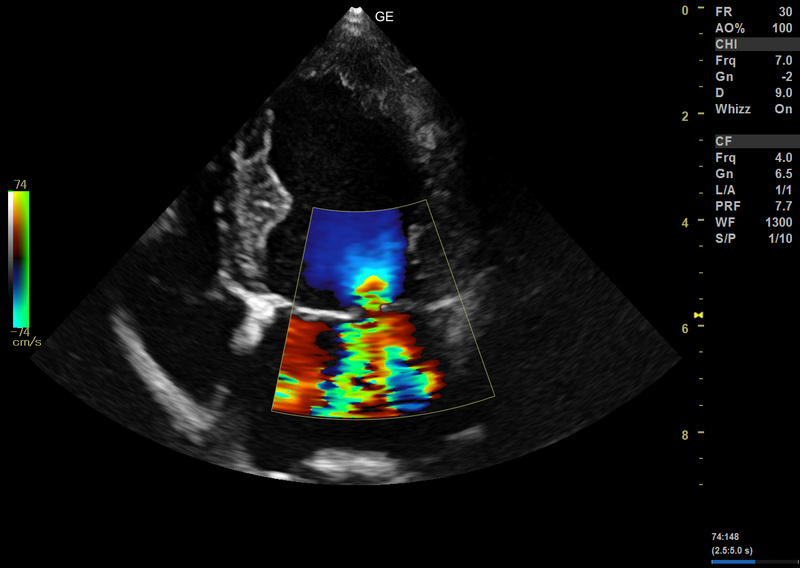

Versana Active™ offre potenza e chiarezza di imaging straordinarie per una maggior sicurezza diagnostica. Consente di avere un'ottima qualità dell'immagine, differenziare i tessuti e delineare le interfacce delle strutture.

- B-Flow™ e Color B-Flow™

Tecnologia di imaging di elevata qualità

Le migliori tecnologie sviluppate da GE in tutti gli ambiti specialistici come cardiologia, muscolo scheletrico, ecografia vascolare sono ora disponibili in un’unica piattaforma: Versana Active™. Scegli la tua versione!